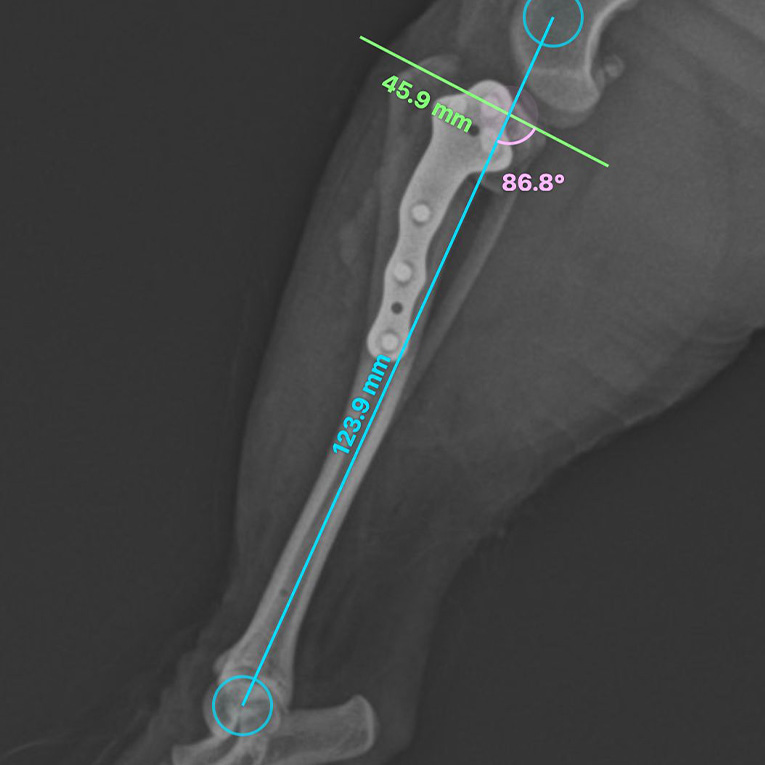

ვეტერინარიუმში ოპერაციის დასაგეგმად კლინიკის მთავარი ვეტერინარი და ქირურგიის განყოფილების უფროსი ლაშა-გიორგი ჯაფარიძე იყენებს ლიცენზირებულ პროგრამას – vPOP PRO (Veterinary Preoperative Orthopaedic Planning). ეს არის მსოფლიოში წამყვანი პლატფორმა ვეტერინარული ორთოპედიული ოპერაციების წინასაოპერაციო დაგეგმისთვის. იგი საშუალებას იძლევა ზუსტად განისაზღვროს მოტეხილობების ხასიათი, ძვლების ზომები, შეირჩეს ოპტიმალური იმპლანტები და წინასწარ შეფასდეს ოპერაციის სავარაუდო შედეგები.

წინა ჯვარედინი იოგის გაწყვეტის ერთ-ერთ ყველაზე ეფექტურ და თანამედროვე მკურნალობის მეთოდად ითვლება ქირურგიული ჩარევა – დიდი წვივის ნიველირებადი ოსტეოტომია (TPLO – Tibial Plateau Levelling Osteotomy). ეს მეთოდი საერთაშორისოდ ოქროს სტანდარტად არის აღიარებული და ხასიათდება მაღალი (90-95%) წარმატების მაჩვენებლით. იგი ძაღლს სრულფასოვან მოძრაობის ფუნქციას უბრუნებს და მნიშვნელოვნად აუმჯობესებს ცხოვრების ხარისხს. მიუხედავად ამისა, მინიატურულ ჯიშებში TPLO საჭიროებს განსაკუთრებულ სიზუსტესა და სკრუპულოზურ წინასაოპერაციო დაგეგმვას.

მინიატურული ჯიშებისთვის TPLO ოპერაციის გაკეთება განსაკუთრებულ სიზუსტესა და სიფრთხილეს მოითხოვს. სწორედ ამიტომ, მისი წარმატებით განხორციელება ხარისხიანი გამოცდილებისა და ტექნოლოგიური მხარდაჭერის შერწყმას საჭიროებს.